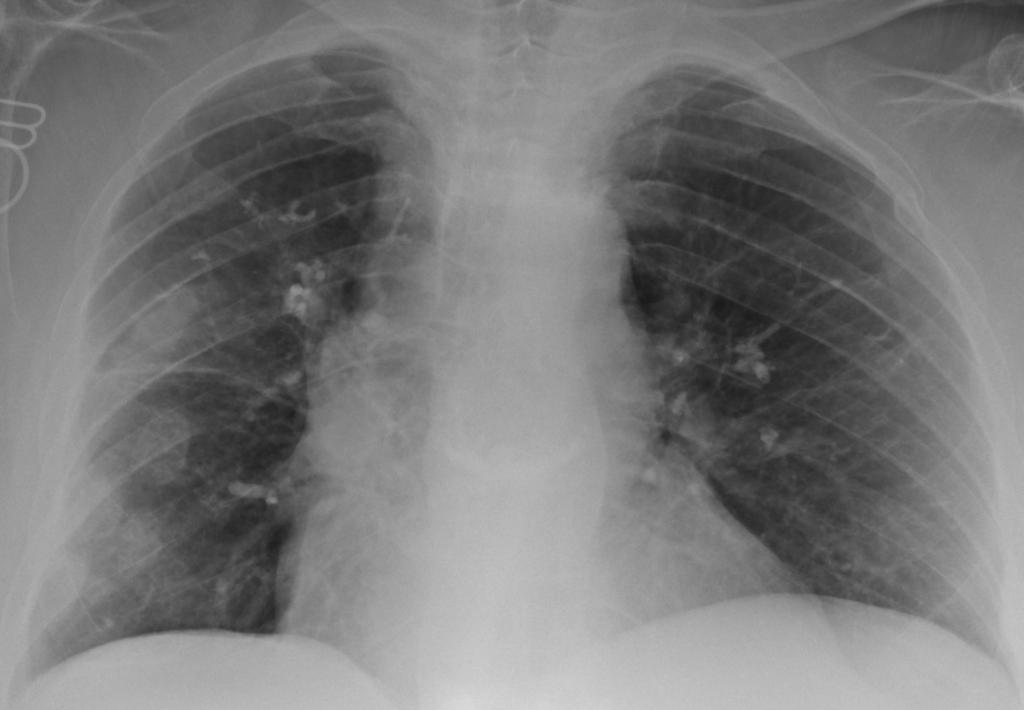

Een 59-jarige vrouw komt naar de Spoedeisende Hulp in verband met koorts en kortademigheid. Haar medische voorgeschiedenis vermeldt onder andere ribfracturen na een ongeval en inzakkingsfracturen. Op een röntgenfoto van de thorax zijn verschillende afwijkingen zichtbaar.

Wat is uw diagnose?